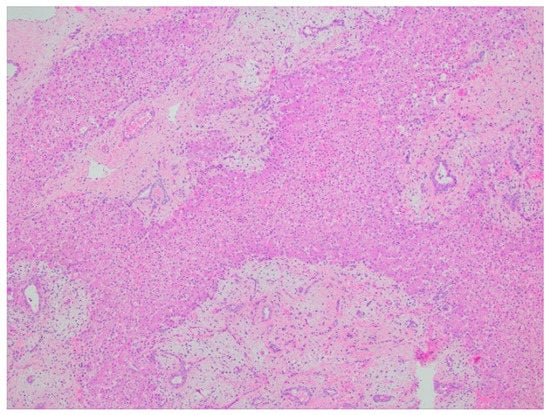

5.2.5. Histopathology and Immunohistochemistry